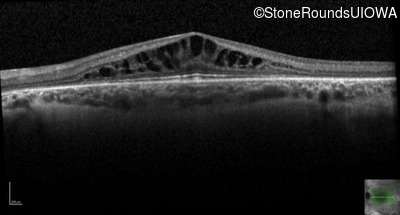

Retinitis Pigmentosa with Anemia (IB10)

OCT Stack

Retinitis Pigmentosa with Anemia

TRNT1

IVS5-26 T>C

Lys416 ins1tggA

AR